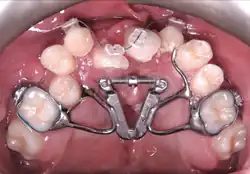

Surgeries on the roof of the mouth early in life typically close the larger hole between the mouth and the nose (caused by the cleft in the palate) but do not repair the defect in the bone, or any holes further forward between the palate and the upper lip. About the age of 8, just before the eye teeth are about to erupt into the bone defect (the cleft), braces are used to first widen the upper jaw, and position the premaxilla. Then, a surgery places bone or a bone substitute in the defect to allow the premaxilla to fuse to the rest of the maxilla, provide bone for eruption of the canine, and close any remaining holes between the mouth and nose. If completed early, the canine teeth will erupt into the mouth with good bone support and remain healthy.

Pre-surgery Orthodontics

In cleft lip and palate cases, the maxilla is typically narrow compared to the lower jaw and must be expanded outward. An expansion appliance is placed in the maxilla 6–9 months prior to correct any crossbite or upper arch constriction.[3] This will widen the cleft size, and so that parents and patients need to be warned the symptoms such as fluid reflux may worsen, although some centres will expand the jaw after surgery is complete. In the case of double clefts, expansion is typically before surgery because the premaxilla needs to be repositioned forward, which cannot occur until the upper jaw is widened to allow room.[4]